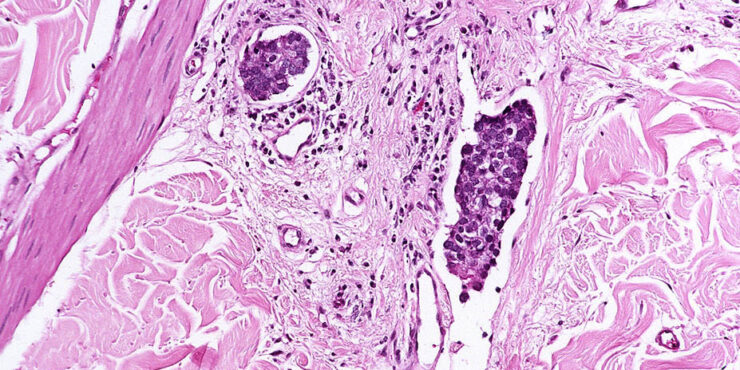

Branchial cleft cyst =كيسة الشق الغلصمي Branchial Cyst (Branchial Cleft Cyst) Sequestration of first or second branchial cleft membranes results in these cysts, sinuses, or tags. EPIDEMIOLOGY Branchial cleft cysts are largely sporadic, but autosomal dominant cases have been reported. There is no gender predominance. Ten percent of lesions are bilateral. ETIOLOGY AND […]